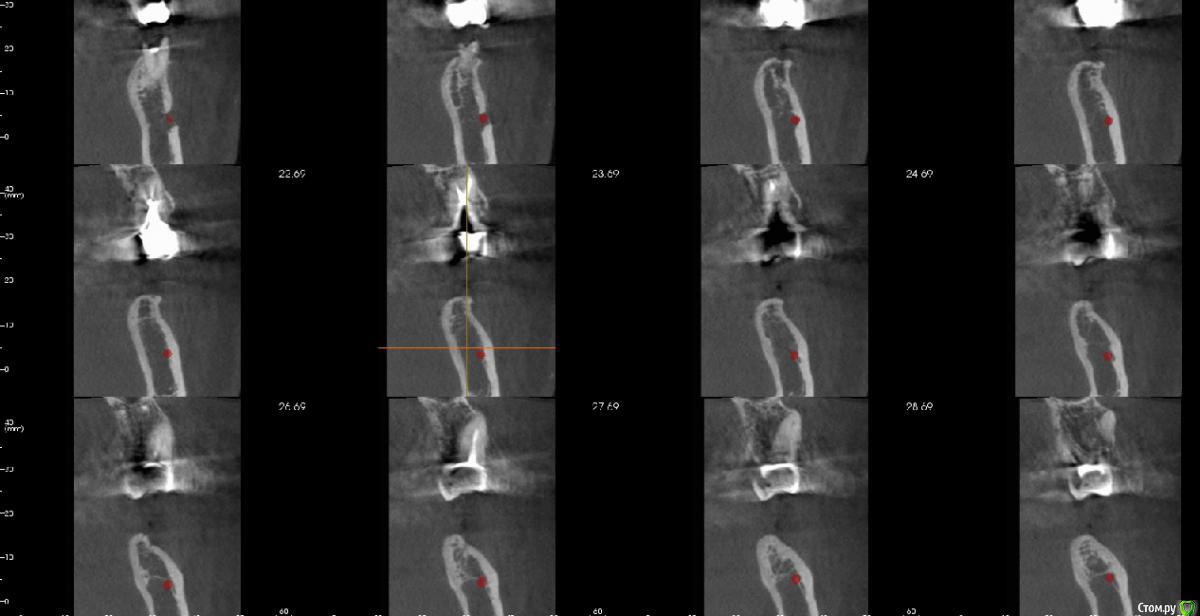

bullbull Опубликовано 28 марта, 2017 Поделиться Опубликовано 28 марта, 2017 Может обсуждалось, но я не нашел. На КТ в области 46, 47 следующая картина. Костный рисунок определяется где-то 8-10 мм. Дальше, как ни играл настройками - пусто (по плотности меньше 50 HU). Соответственно, и канал не визуализируется.Как быть? Ссылка на комментарий

gum Опубликовано 28 марта, 2017 Поделиться Опубликовано 28 марта, 2017 Я вижу и канал и костный рисунок. Канал почти в самом низу. Могу конечно ошибаться(повертеть надо). Ссылка на комментарий

АнтонТЛТ Опубликовано 28 марта, 2017 Поделиться Опубликовано 28 марта, 2017 Посмотри на саггитальном срезе, канал должен быть виден, хотя бы его нижняя граница Ссылка на комментарий

Bier Опубликовано 29 марта, 2017 Поделиться Опубликовано 29 марта, 2017 Я вижу и канал и костный рисунок. Канал почти в самом низу. Могу конечно ошибаться(повертеть надо).скорее всего это ошибка, я тоже там вижу просветление. Но слишком уж низко для этой зоны. Хотя может конечно. Ссылка на комментарий

Irouil Опубликовано 29 марта, 2017 Поделиться Опубликовано 29 марта, 2017 На первом срезе (левый верхний) я на 99% уверен что канал видно - слишком уж правильный контур. Плюс я бы, конечно, все таки с мезио-дистального среза пошел, как и Антон советовал - имея первую реперную точку на вестибуло-оральном срезе и отстреливаясь выше нижней стенки можно построить пусть и не идеально, но примерно канал Ссылка на комментарий